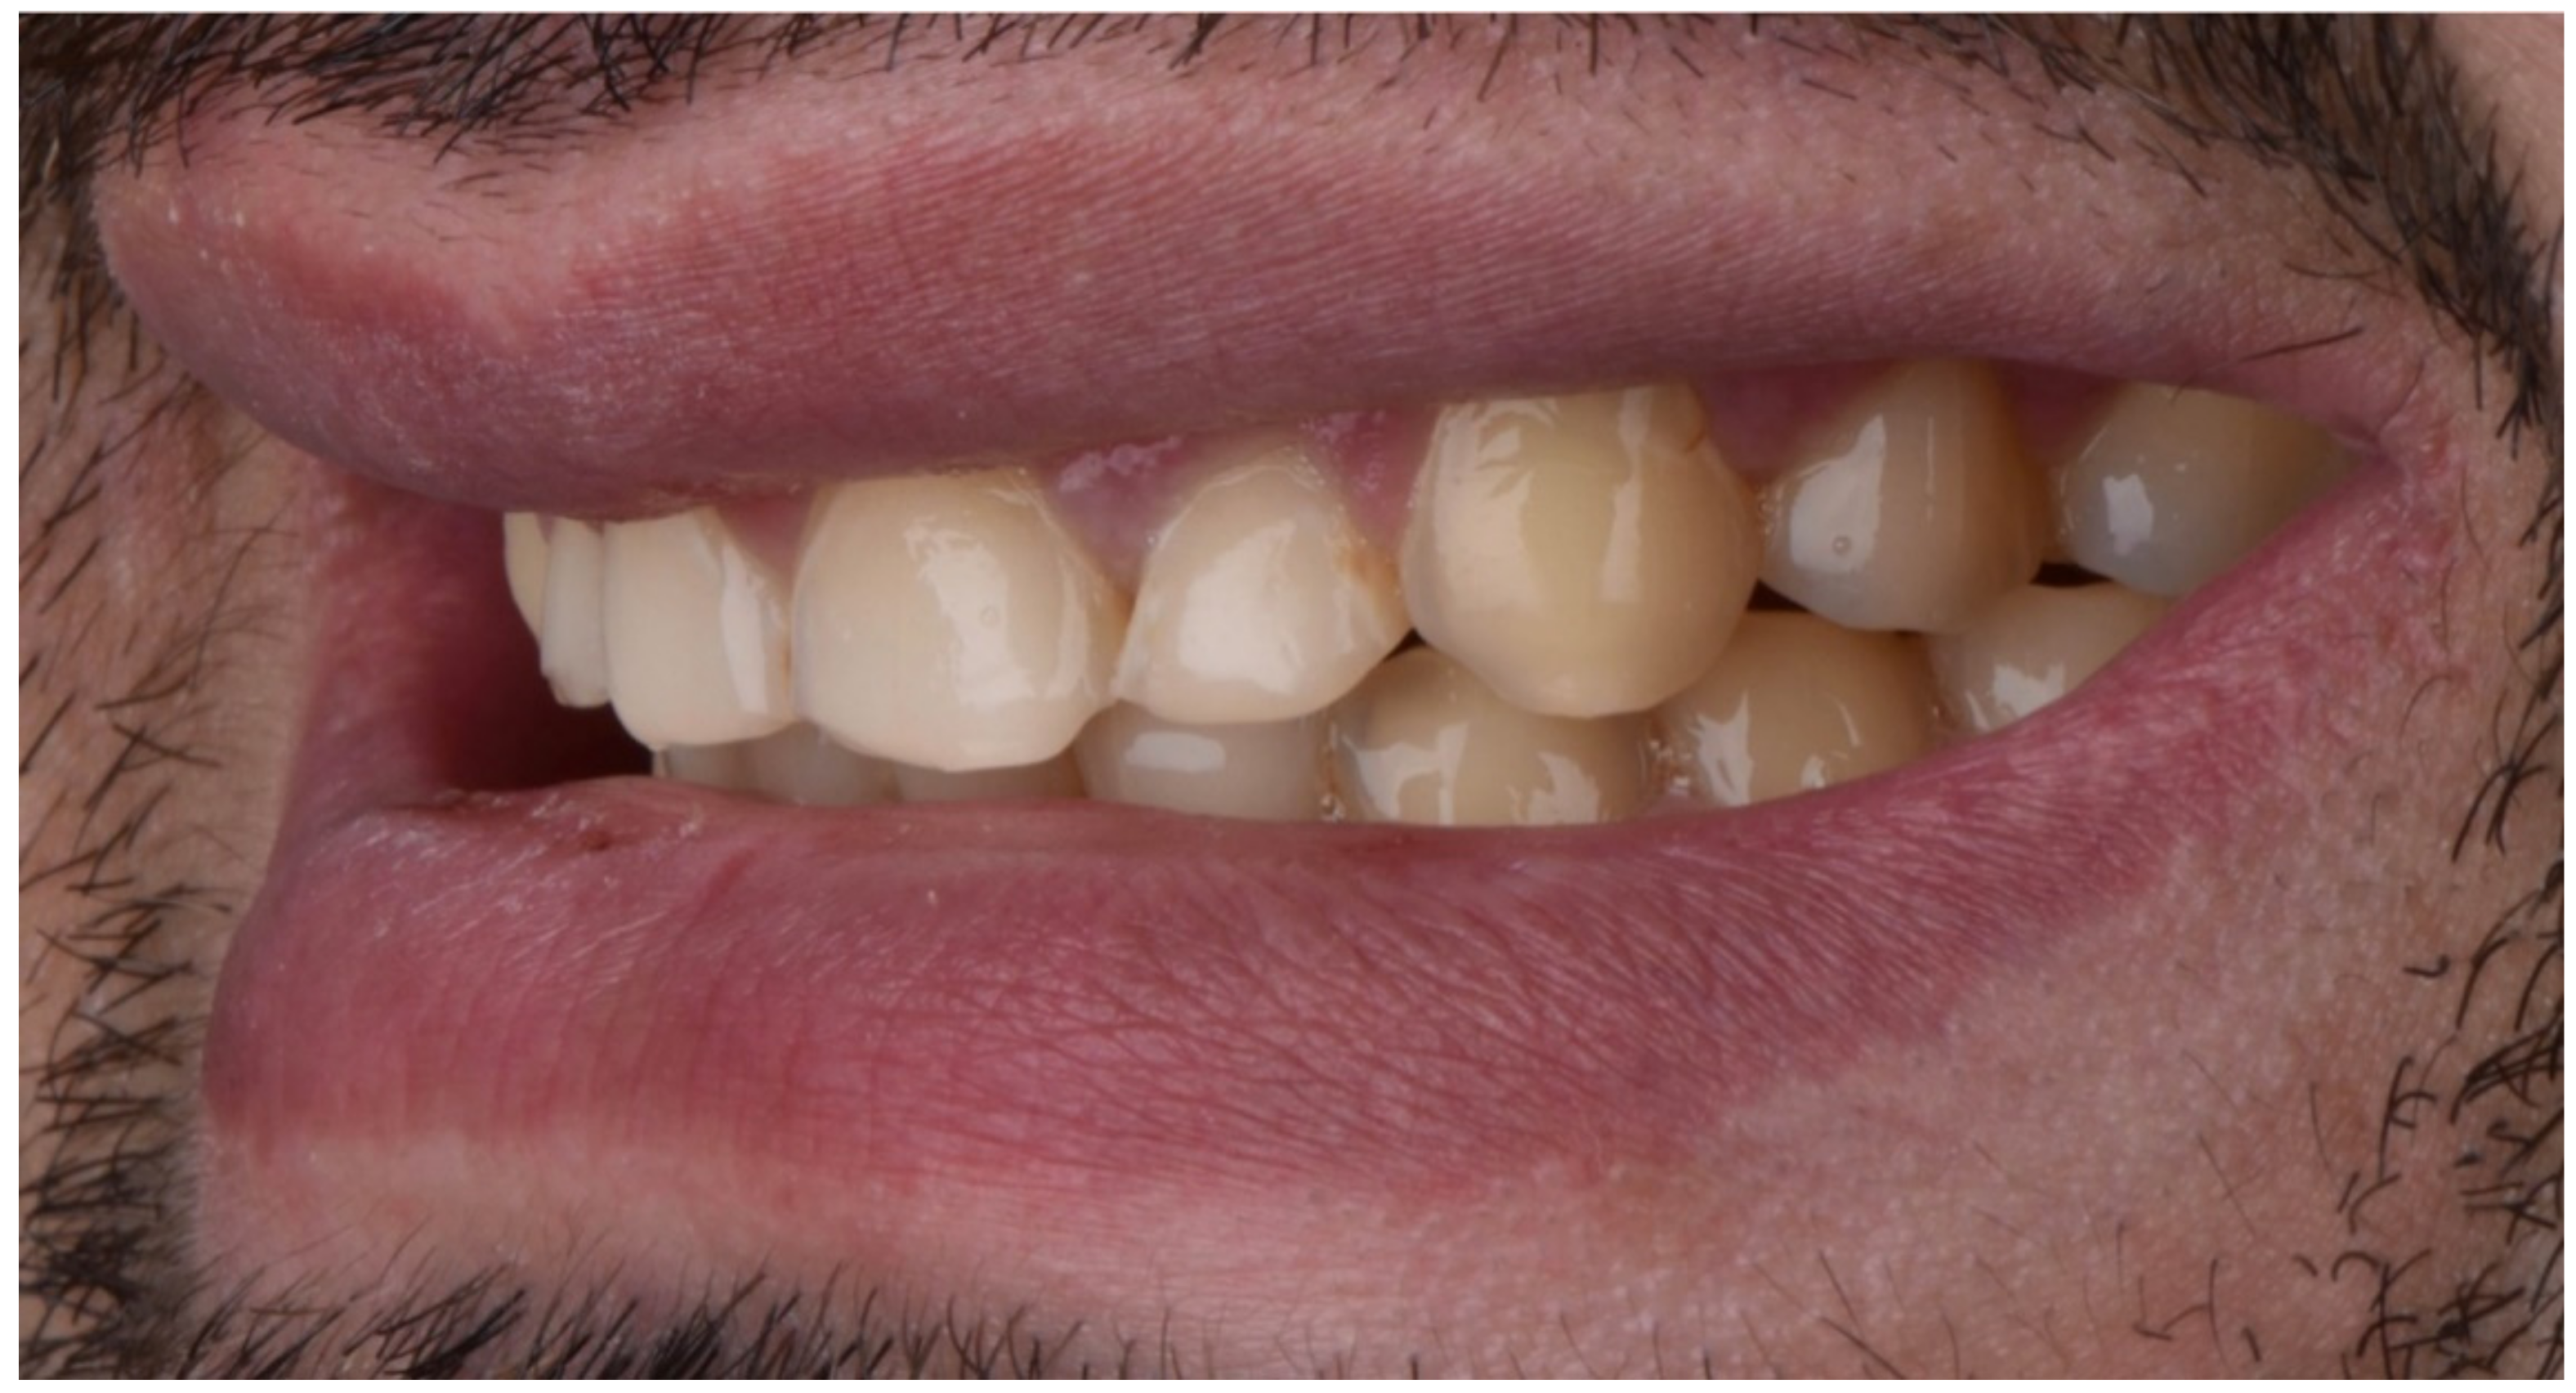

2.2. Restorative Phase